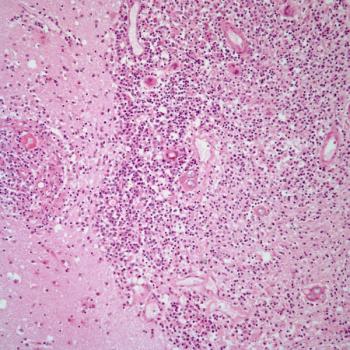

A 38-year-old woman presents with abdominal pain, and a biopsy is performed. What is your diagnosis?